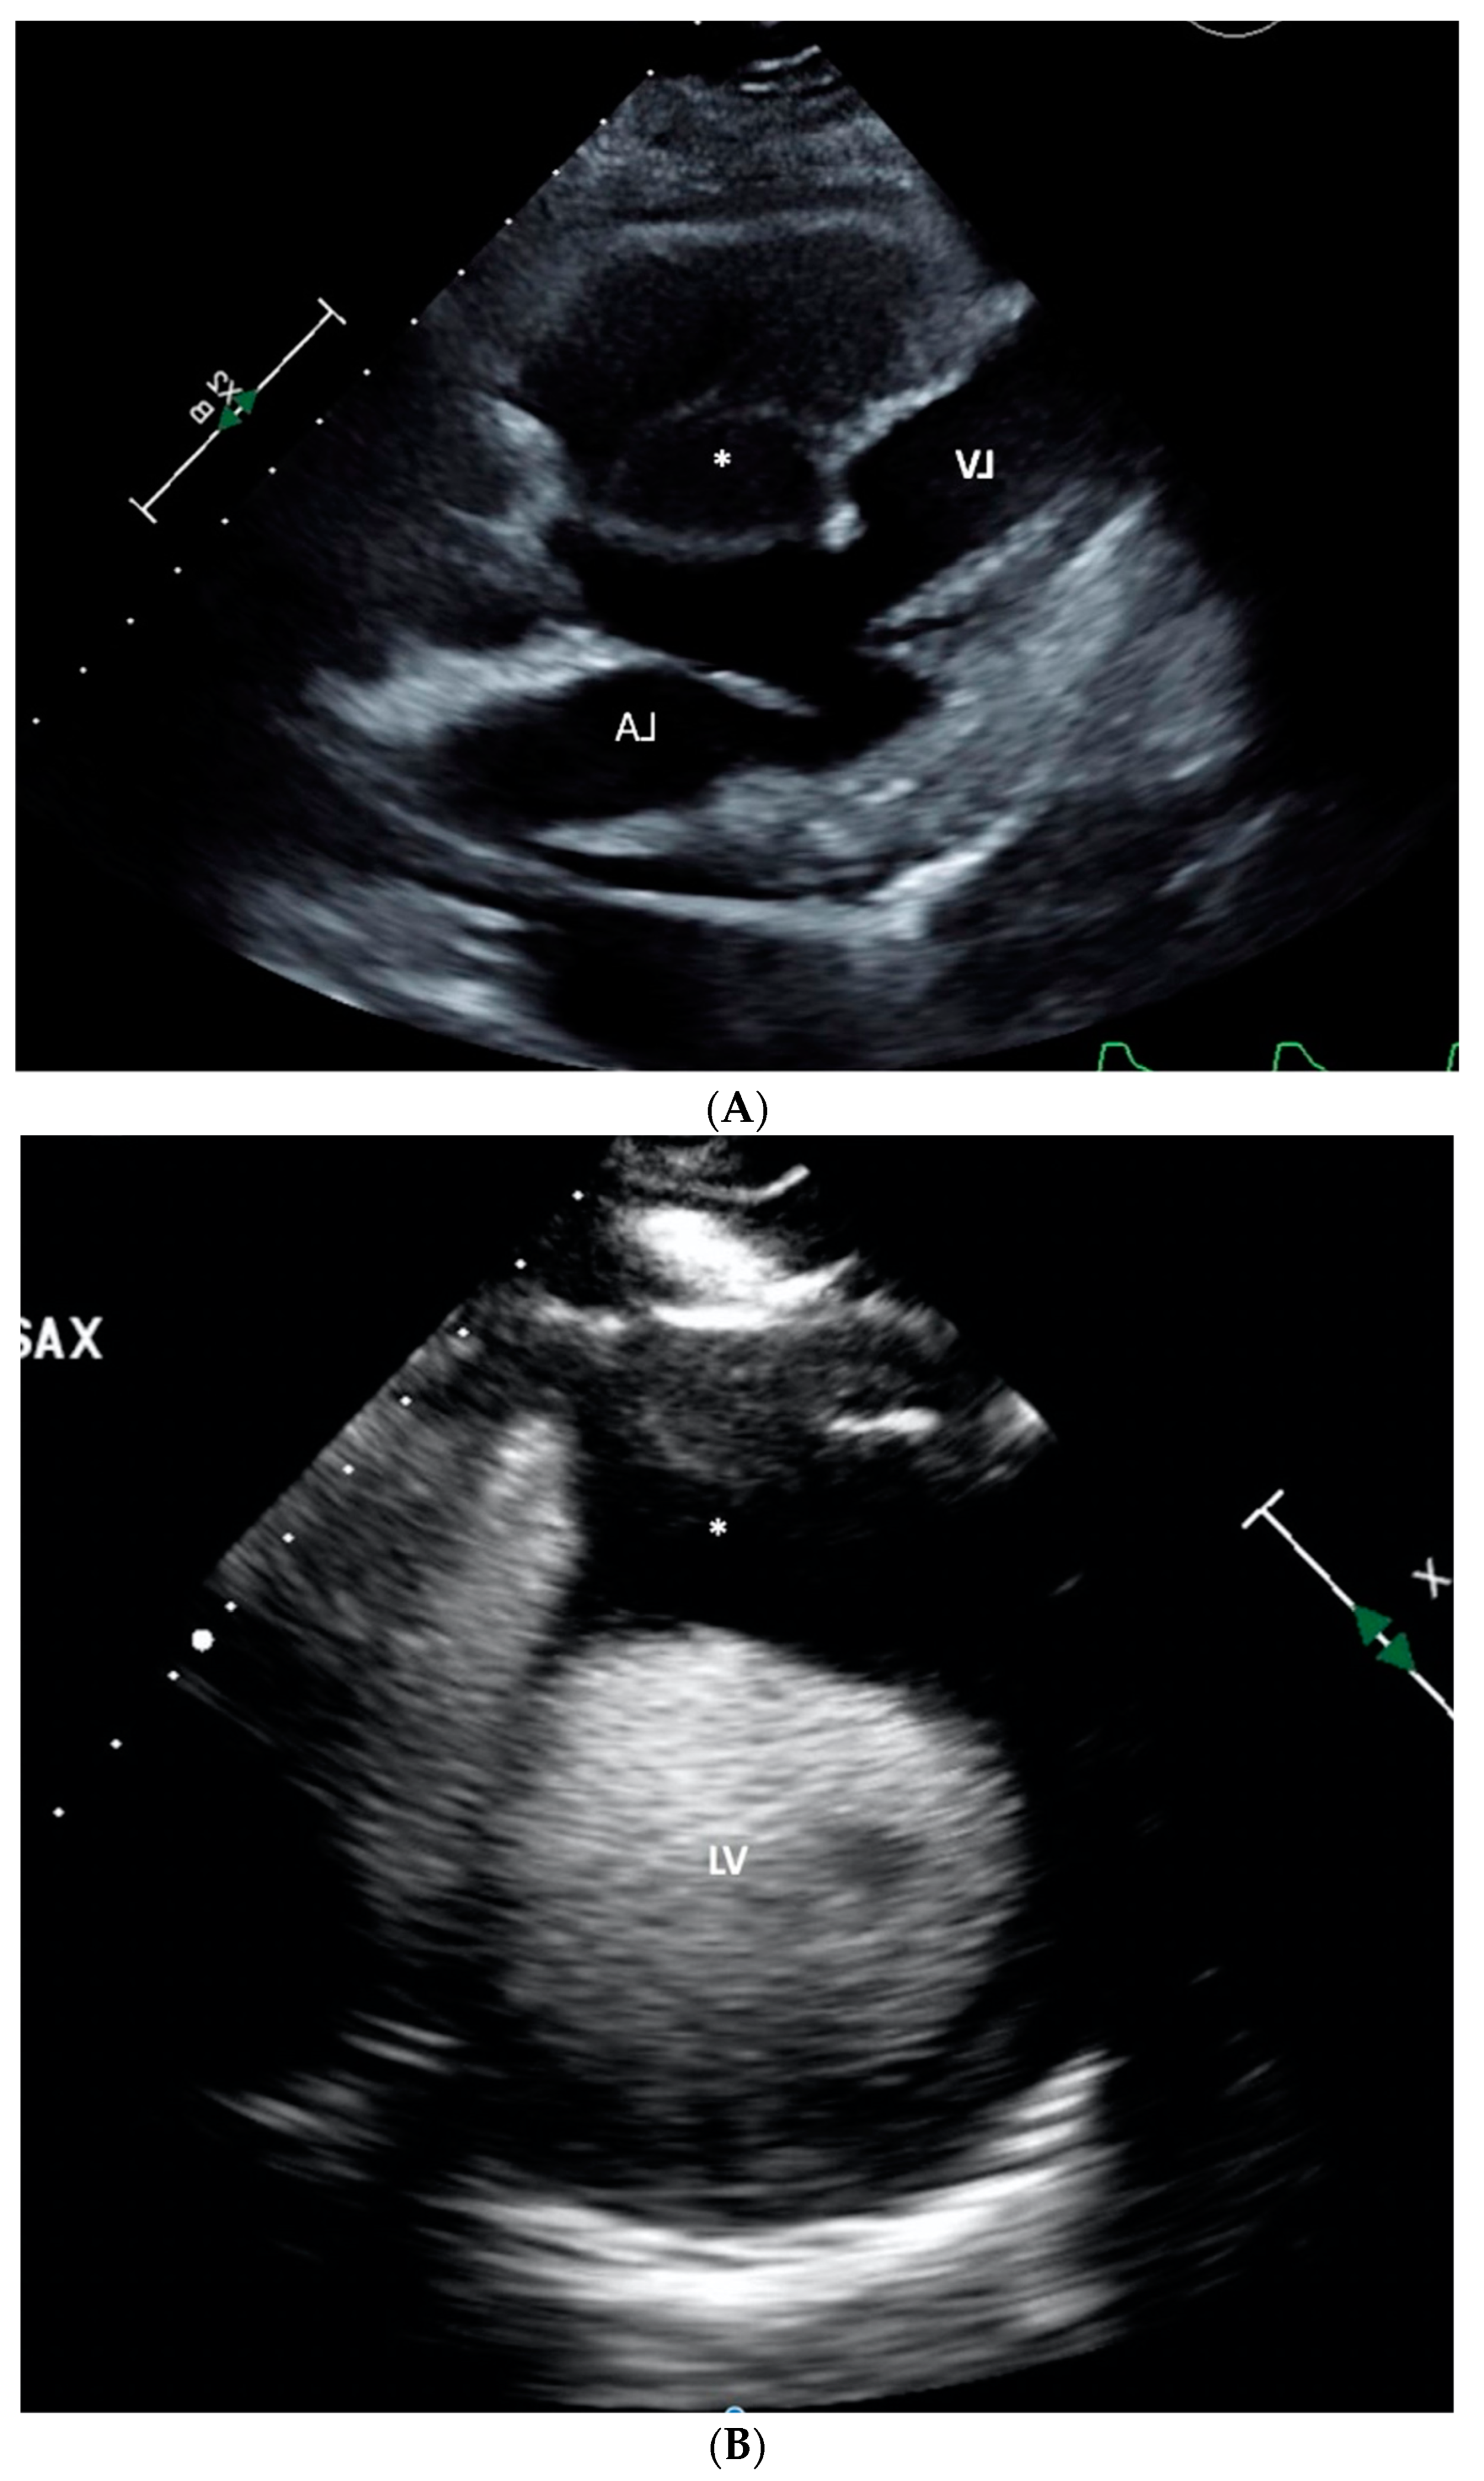

The angiographic findings suggested external compression as the likely cause of the 80% lesion in the mid LAD. This assumption gained credence when considering the non-invasive imaging results. Transthoracic echocardiogram showed normal left ventricular chamber diameter and systolic function with an ejection fraction of 50-55%, but was significant for notable septal wall thickening (Figure 3A–C). A subsequent PET/CT scan demonstrated an FDG-avid focus aligning with a heterogeneously enhancing mass along the interventricular septum of the heart, measuring approximately 3.1 x 2.8 cm, representing a significant change from her previous scan (Figure 4A,B). A post-procedural CT scan, performed after the emergent coronary angiogram and pacemaker implantation, revealed significant interventricular septal thickening corresponding to myocardial metastases (Figure 5A), a contrast to a CT performed approximately five months prior, which indicated normal septal thickness (Figure 5B).

Figure 3. A: Transthoracic echocardiogram (TTE) in parasternal long axis with left ventricle (LV) and left atrium (LA) for orientation, severely thickened interventricular septum (*) appreciated. B: TTE in the parasternal short axis with ultrasound contrast. Left ventricle (LV) with severely thickened anterior septum (*). C: TTE again in parasternal long axis with ultrasound contrast. Left ventricle visible (LV) for orientation and significantly thickened septum (*).